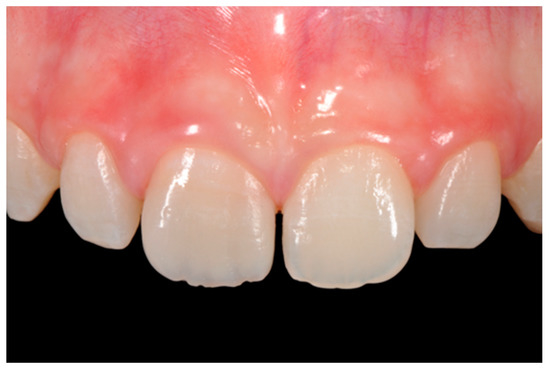

Figure 1.

Initial clinical situation. Reprinted from Restauri diretti nei settori anteriori, G. Paolone, S. Scolavino, © 2021, with permission from Quintessence Publishing Italy.